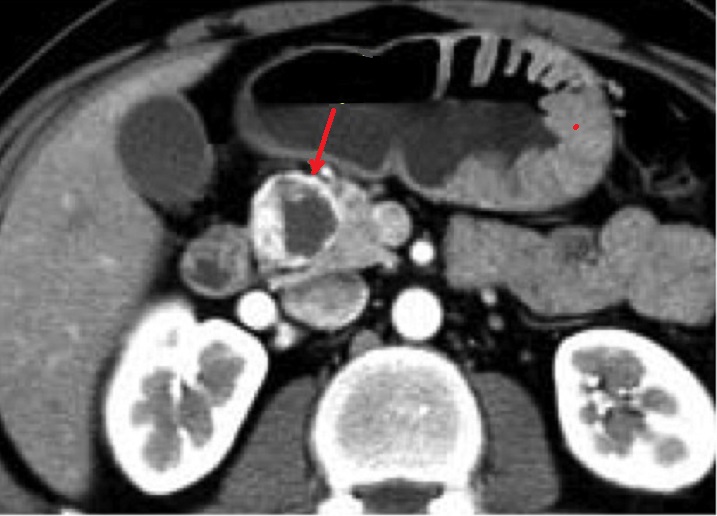

Plus rare , les tumeurs

du pancreas endocrines fontionelles peut de forme

kystique ( fleche rouge ) moins de secretion de

endocrine et peut en presente de nodule calcifie..

La tumeur est hyperdense et sa contenue etre

hypodense |